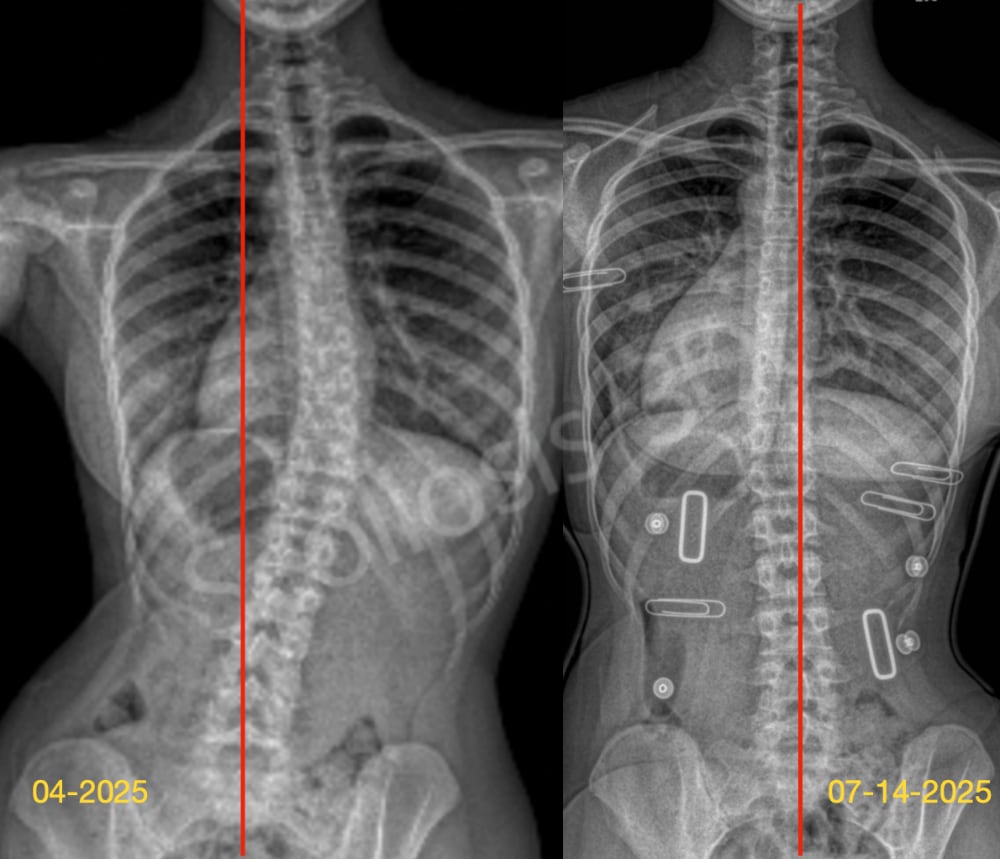

مدة وطريقة ارتداء حزام اعوجاج العمود الفقري: سر نجاح العلاج وتجنب الجراحة بنسبة% 95 عند تشخيص المراهق باعوجاج العمود الفقري مجهول السبب، يبدأ الأهل رحلة مليئة بالأسئلة حول مدى نجاح العلاج بالحزام الطبي. واحدة

السر لنجاح حزام اعوجاج العمود الفقري حتى% 90 :تحسن زاوية كوب وانحراف الفقرة القمية عند تشخيص المراهق باعوجاج العمود الفقري مجهول السبب، يبدأ الأهل بطرح سؤال مهم: هل سينجح العلاج بحزام اعوجاج العمود الفقري